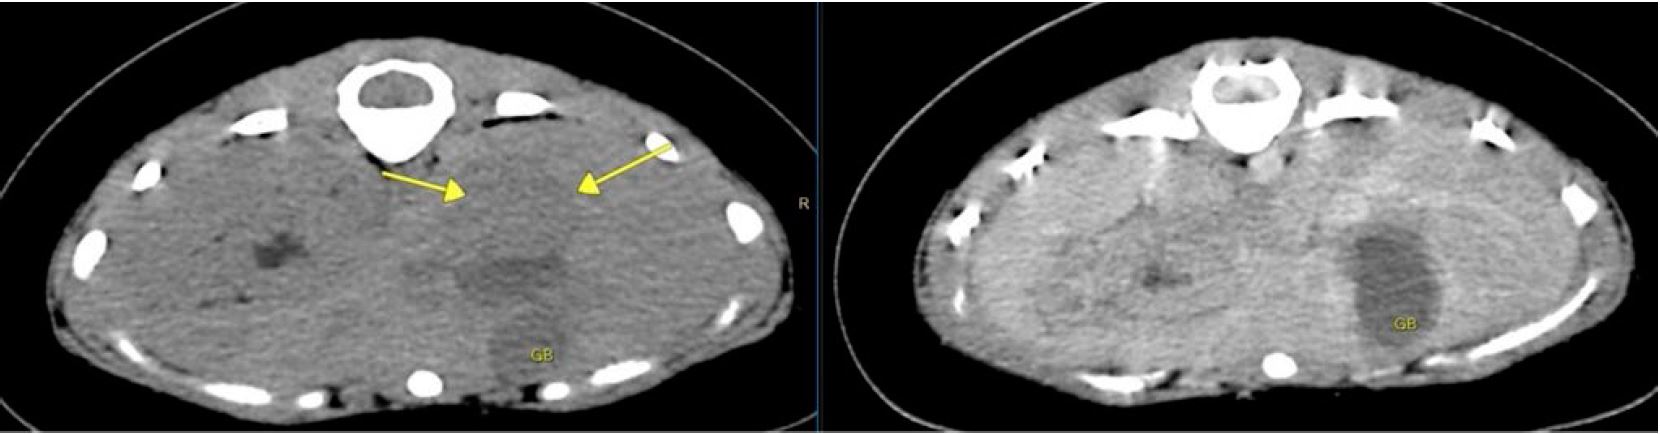

КТ показала чітку або повну оклюзію лівого зовнішнього слухового проходу внаслідок потовщення м’яких тканин (мал. 1). Крім того, ліва барабанна трубка була заповнена м’якою тканиною. Права була нормально заповнена повітрям.

На малюнках 1a і 1b показано слуховий прохід пацієнта в кістковому фільтрі (жовті стрілки).

На аксіальних зображеннях видно вузький слуховий прохід (а), виражене звуження лівого зовнішнього слухового проходу (б), набряк м’яких тканин лівого зовнішнього слухового проходу на постконтрастному скануванні та набряк м’яких тканин у лівій барабанній порожнині. Звужений зовнішній слуховий прохід з потовщеною і неправильною стінкою сумісний з інфекцією зовнішнього вуха. Ослаблення м’яких тканин лівої порожнини вказує на середній отит (запалення середнього вуха).

Малюнок 1c і 1d. На малюнку 1c показано заблокований слуховий прохід у фільтрі м’яких тканин, а на малюнку 1d показано заповнену рідиною порожнину в кістковому фільтрі.